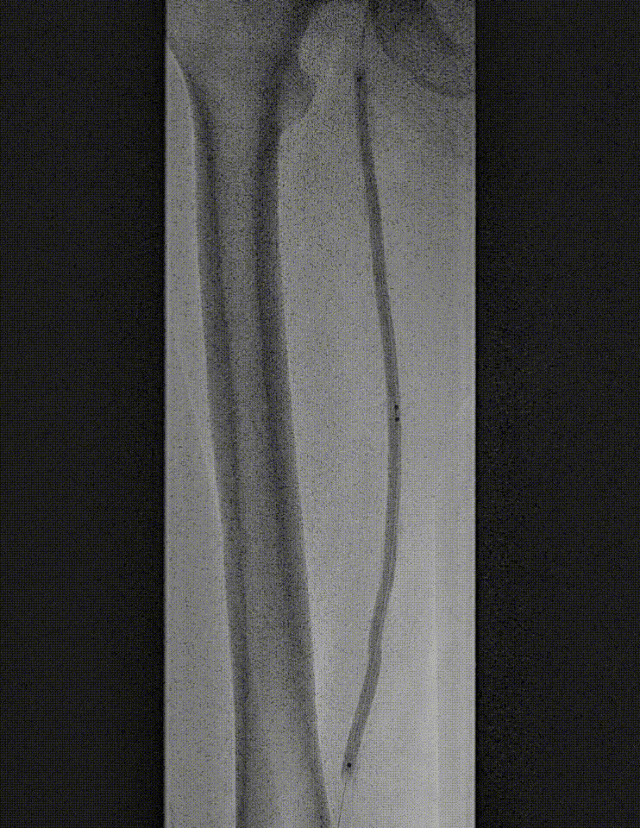

图:DA 造影+通过病变

图:造影及通过病变